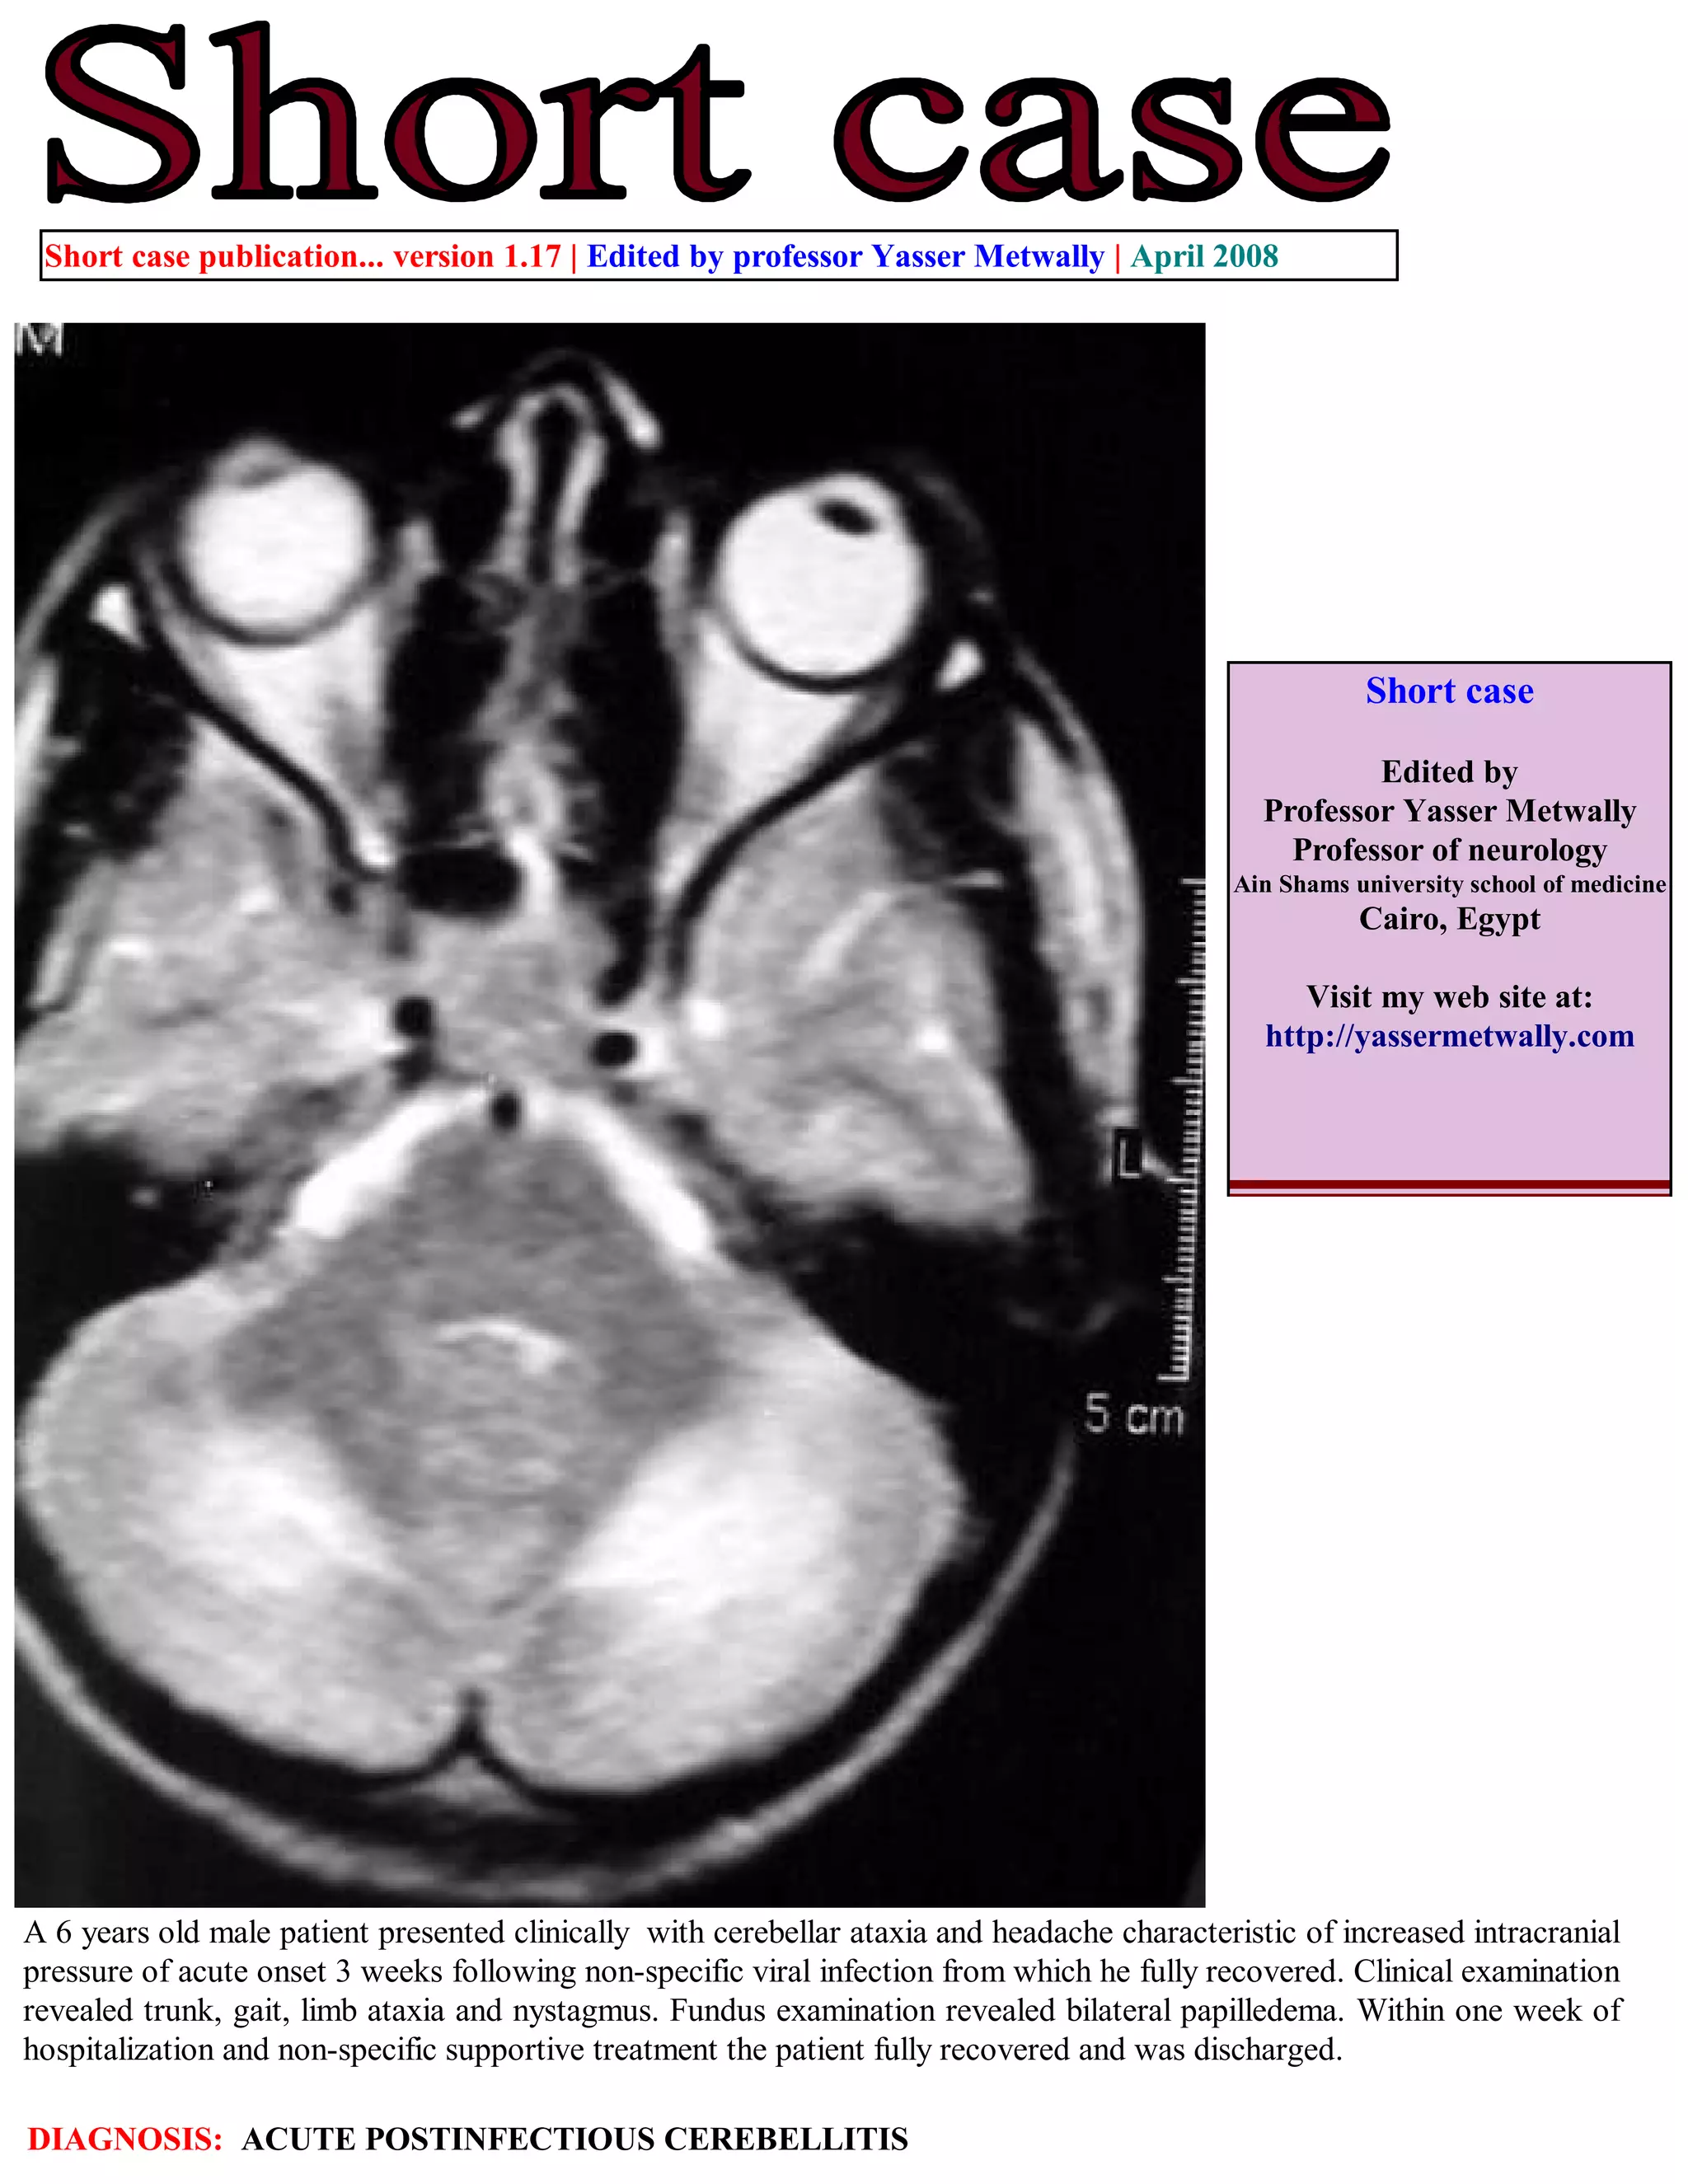

This document summarizes a case study of a 6-year-old male patient who presented with cerebellar ataxia and headache 3 weeks after a viral infection. Clinical exams revealed trunk and limb ataxia, nystagmus, and papilledema. Brain scans showed bilateral symmetrical lesions in the cerebellar white matter. The patient was diagnosed with acute postinfectious cerebellitis and fully recovered within a week of supportive treatment. The case study is intended to demonstrate the characteristic MRI findings of postinfectious cerebellitis.